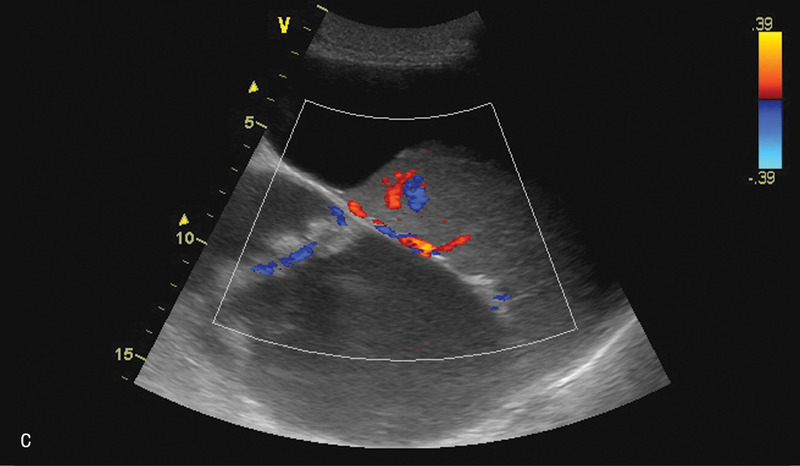

Po kolejnych 3 tygodniach nastąpiło nasilenie dolegliwości sugerujących zaostrzenie zapalenia (wymioty, bóle brzucha, wzdęcie). Pacjenta ponownie przyjęto na oddział chirurgiczny. Rozpoznanie nawrotu zapalenia potwierdzono w badania laboratoryjnych. Wykonano badanie USG, które wykazało obecność kilku zbiorników płynu w śródbrzuszu, w rzucie trzustki oraz po stronie lewej w nadbrzuszu i w lewej jamie opłucnowej (ryc. 2).

Rycina 2. Badanie USG jamy brzusznej. A. Przekrój poprzeczny przez nadbrzusze. Widoczny hipoechogeniczny zbiornik płynu w rzucie głowy trzustki, przesłonięty powierzchownie przez dwunastnicę. B. Przekrój podłużny przez nadbrzusze. Widoczny opisywany grubościenny zbiornik płynu w śródbrzuszu. W centralnej części widoczne zmiany otoczone płynem naczynia. C. Przekrój podłużny przez lewe podżebrze. Widoczne kolejne zbiorniki płynu w otoczeniu śledziony oraz w rzucie trzonu żołądka.